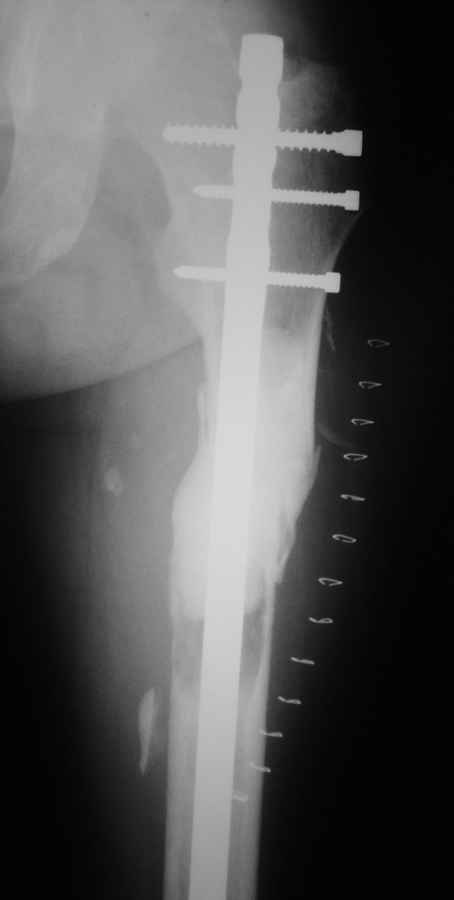

[Ortho] Патологический перелом бедра

Добрый день. Подобное наблюдение было у меня. Надежная операция, довольный больной.

Имя     : май2010 (2).JPG